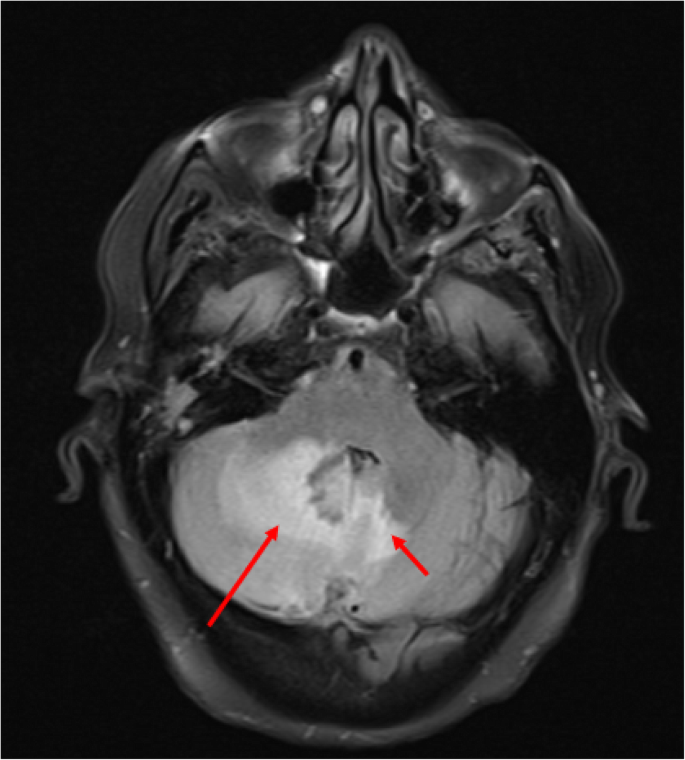

Axial T2 FLAIR sequence MRI at the level of the 4th ventricle within the posterior fossa demonstrating diffuse right cerebellar hyperintensity (long red arrow) and to a lesser extent left cerebellar hemisphere hyperintensity (short red arrow) corresponding to the large amount of vasogenic edema produced by the lesion